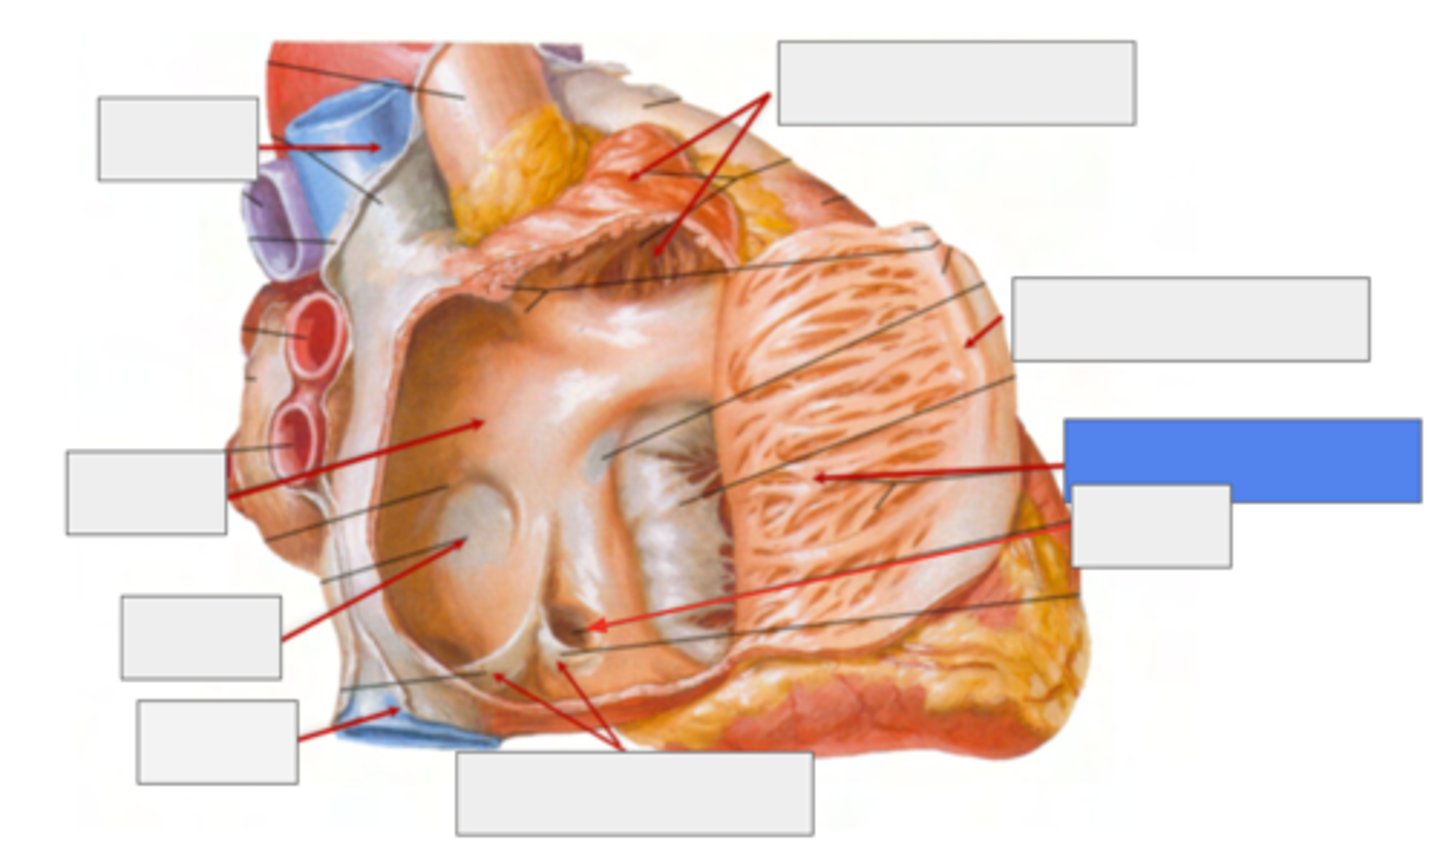

What is pointing the blue square?

valves of inferior vena cava and coronary sinus